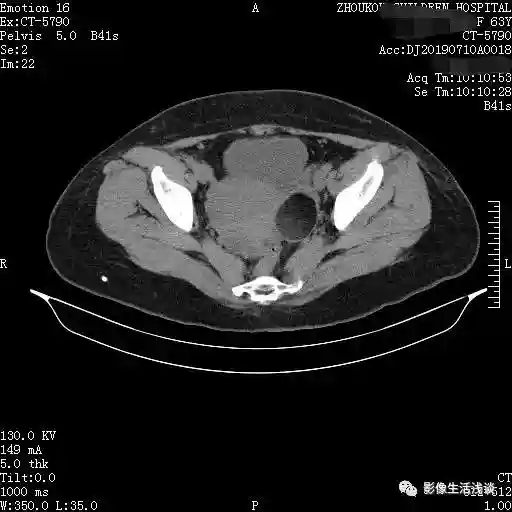

第二个病例女性63岁,体检CT中发现盆腔内左附件区囊性占位:

通过以上病例我们可以发现卵巢畸胎瘤CT表现,大部分情况下是呈多个囊性的病变,囊内套囊。每个囊的信号或者密度是不相同的,各个囊内的内容物也是不相同的。影像学常见的主要是脂肪、液体及骨骼等内容物,有一定的特征性的密度信号。在此情况下就提示是畸胎瘤,部分囊可以见到有头节形成的结节或肿块。如果囊壁的结节比较大呈肿块型,边缘不规则,囊外有侵犯有可能是恶性的。增强扫描囊壁与结节之间可有轻度或中度的强化,根据相应的CT的表现,同时也要结合女性相应的肿瘤标志物、临床表现,来给予综合的判断以及后续的处理,做到早发现早处理,降低恶性畸胎瘤的发病率。